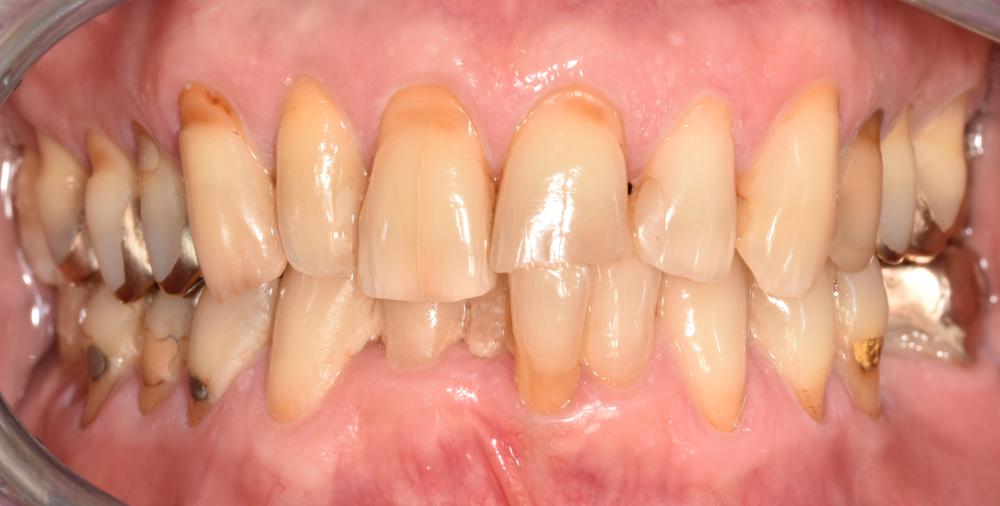

Klinisches Beispiel (Abb. 1a-f)

Präventive Interventionen beinhalten in ihrer Gesamtheit physikalisch-mechanische, chemisch-pharmakologische und biologisch-diätetische Maßnahmen, die individuell auf die psychosozialen Gegebenheiten und Bedürfnisse der Patienten angepasst werden sollten. Auch bei Senioren und Hochbetagten gilt es, die aktuellen Leitlinien und Handlungsempfehlungen für die Biofilmkontrolle und Kariesprophylaxe zu beachten: Zur Biofilmkontrolle sollen Patienten mindestens zweimal täglich mit einer fluoridhaltigen Zahnpasta ihre Zähne putzen. Dabei können je nach Patient unterschiedliche manuelle oder elektrische Zahnbürsten zum Einsatz kommen (11). Ebenso soll fluoridhaltige Zahnpasta mit einer Fluoridkonzentration von mindestens 1.450-1.500 ppm F- verwendet werden. Hochbetagte Patientinnen und Patienten, die zu den vulnerablen Gruppen gehören, haben oftmals ein hohes Karies- und insbesondere Wurzelkariesrisiko (s. Abb. 1). Wurzelkaries schreitet sehr schnell voran und ein zügiges präventives Eingreifen ist von Nöten, um den erkrankten Zahn langfristig zu erhalten. Hier bietet es sich an, auf spezielle Präparate mit hochkonzentrierten Wirkstoffen zurückzugreifen. Empfehlenswert ist zunächst die häusliche Anwendung einer hochkonzentrierten Zahnpasta mit 5.000 ppm F- (Duraphat® Zahnpasta), die rezeptpflichtig ist und dem Patienten ein- bis zweimal pro Jahr von der Zahnärztin oder dem Zahnarzt verordnet werden kann. Es hat sich jedoch gezeigt, dass die Aufrechterhaltung präventiver Interventionen (regelmäßiges Recall, hochfluoridierte Zahnpasta) insbesondere bei Menschen mit schwerer Demenz deutlich limitiert ist (12). Eine umfassende Metaanalyse konnte zeigen, dass 5%iger NaF-Lack am wirksamsten zur Verhinderung oder Remineralisierung nicht kavitierter kariöser Läsionen an bukkalen und lingualen Flächen war (13). Daher sollte bei hohem (Wurzel-)Kariesrisiko eine regelmäßige Applikation von hochkonzentriertem Fluoridlack (22.500 ppm) erfolgen. Das Auftragen von Chlorhexidin-Lack auf die Wurzelkariesläsionen hat sich bei Patienten, die nicht mobil sind und keine Zahnarztpraxis mehr aufsuchen können, als wirksam erwiesen und könnte bei pflegebedürftigen und bettlägerigen Patienten ebenfalls Anwendung finden (14).

Abb. 1: 85-jähriger Patient mit 27 eigenen natürlichen Zähnen, der das WHO-Kriterium für erfolgreiches orales Altern (mindestens 20 eigene natürliche Zähne im Alter von 80 Jahren) erfüllt. Der Patient leidet an Hypertonie, nimmt Metoprolol dagegen ein, ist allergisch auf verschiedene Desinfektionsmittel und hat Heuschnupfen. Er hat keinen Pflegegrad und ist in seiner täglichen häuslichen Mundhygiene nicht einschränkt. Er sucht seine Zahnärztin in regelmäßigen Abständen zur Routinekontrolle auf, putzt sich zweimal täglich die Zähne mit einer fluoridhaltigen Zahnpasta (1.450 ppm F-) und nutzt täglich individuell angepasste Interdentalraumbürstchen. Vermehrt berichtet er von Mundtrockenheit und trockenen Augen.

a) Ansicht von frontal in habitueller Okklusion; b) Seitenansicht rechts in habitueller Okklusion; c) Seitenansicht links in habitueller Okklusion; d) Aufsicht des Oberkiefers; e) Aufsicht des Unterkiefers; f) Zahn 16 zeigt palatinal an der Grenze zur bestehenden Kompositrestauration eine Wurzelkaries, die im Sinne einer Reparaturrestauration mit Komposit restaurativ versorgt werden kann.

Bilder: Frese, © mit freundlicher Genehmigung des UKHD